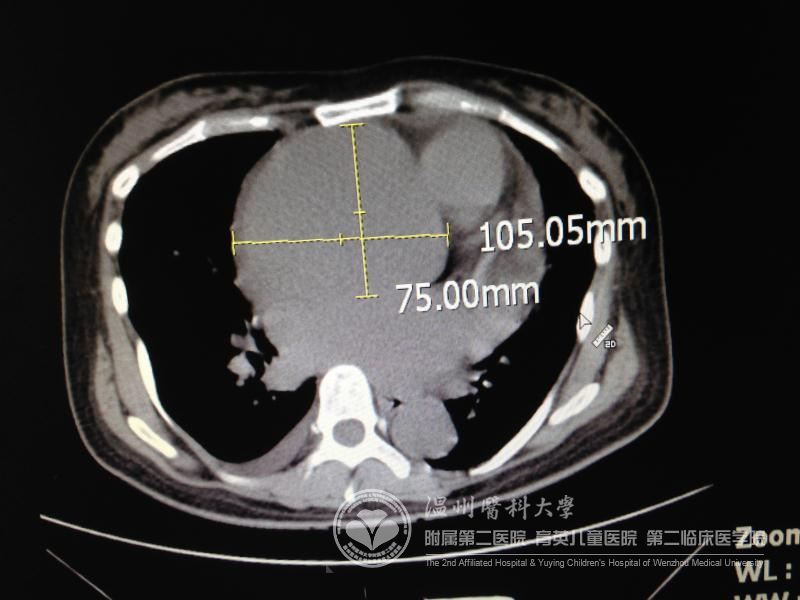

曲女士体内主动脉夹层已存在两年以上,因为经济原因,一直不能得到有效救治。病人入院时病情非常危重,胸部CT显示:升主动脉处形成一个直径达10cm的瘤体,累及主动脉弓,造成心脏严重扩大。患者极度痛苦,连睡觉都不能平卧。